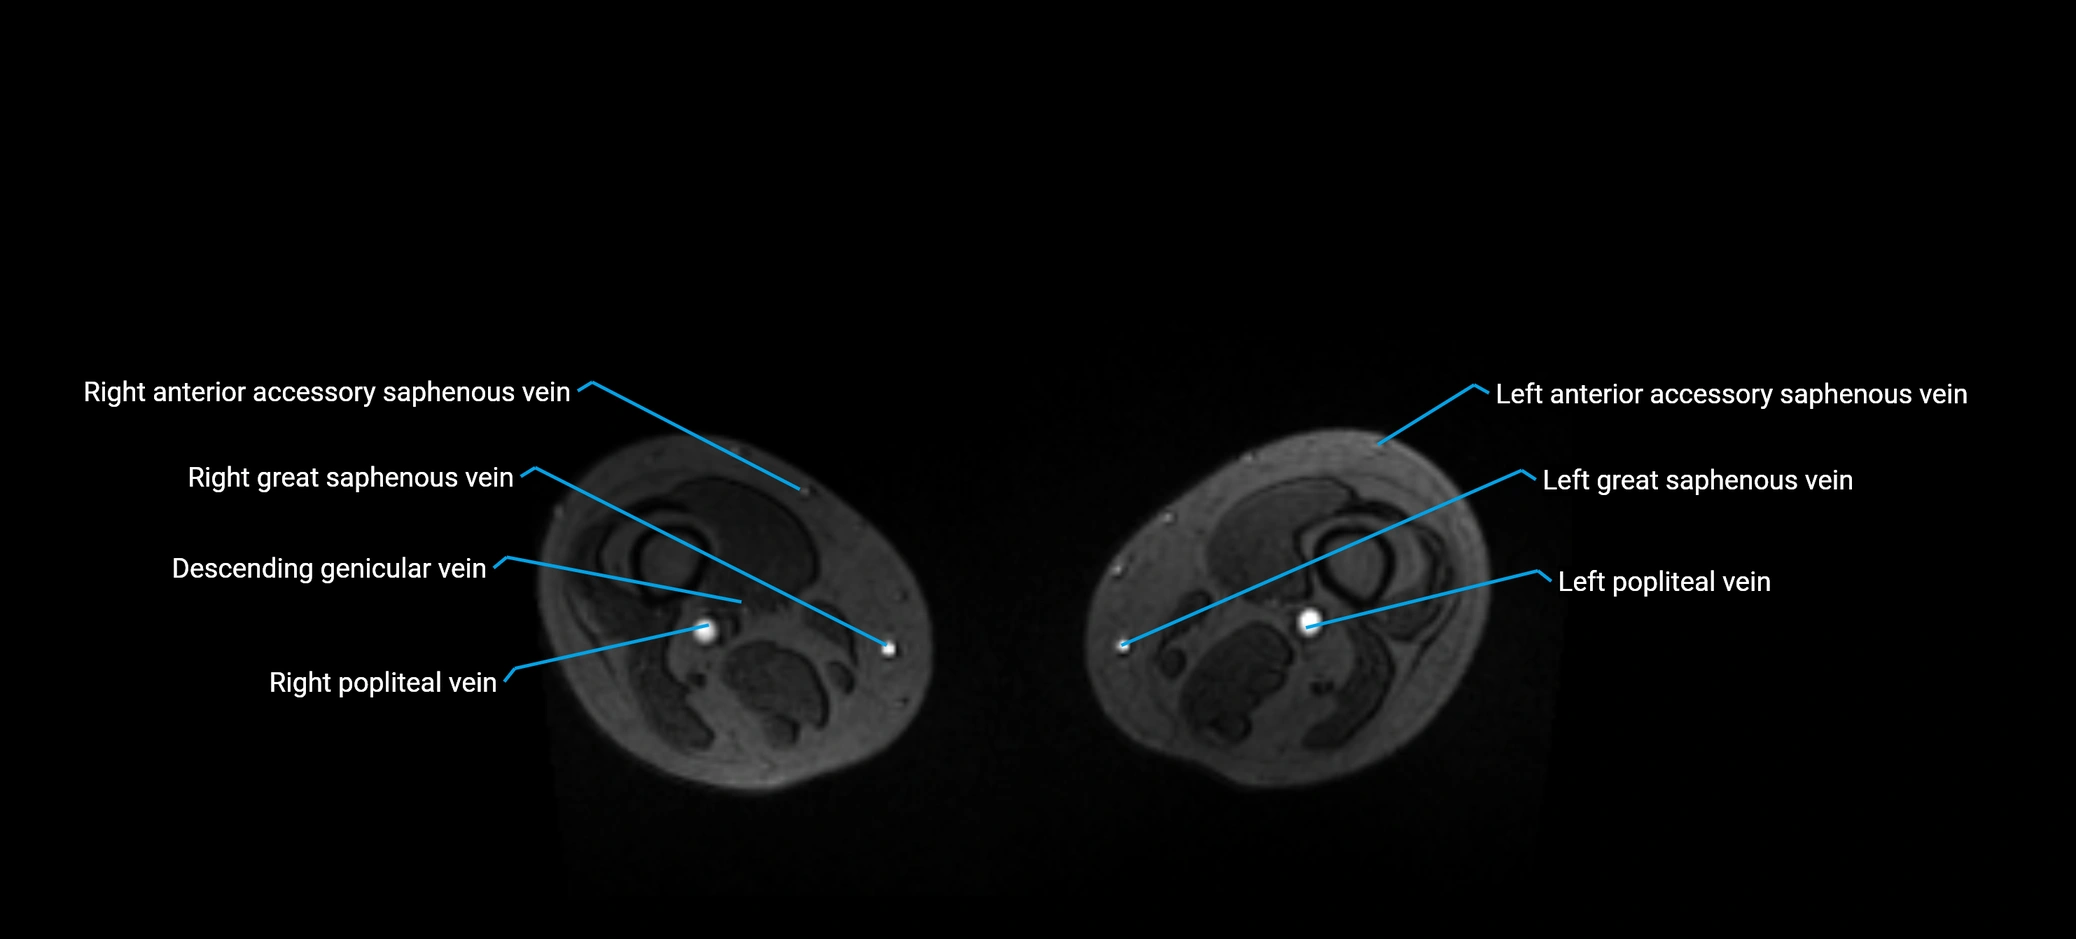

MRI image

image